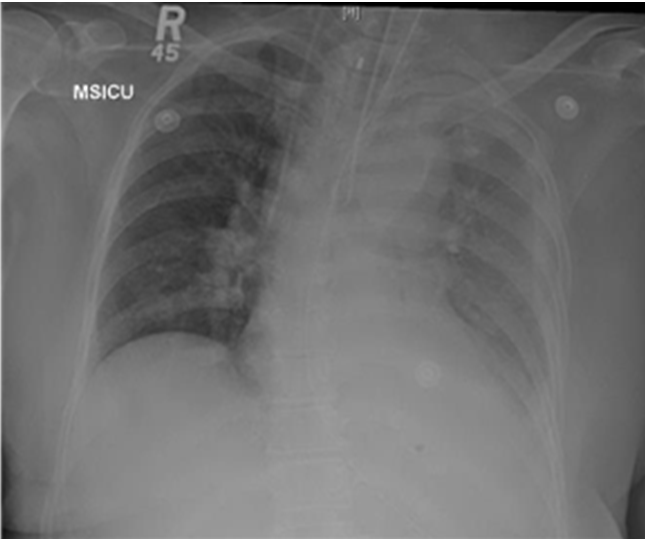

On day-10 postoperatively, the patient started complaining of abdominal pain, her heart rate was increasing up to 130 bpm, as well as her respiratory rate 25/min, and she had fever reached 38.5°C. The patient was transferred to the ICU then, intubated and sedated; work-up done to diagnosis sepsis. The patient was started on empirical IV antibiotics. Chest X-ray was done and revealed pleural effusion for which a pig tail catheter was inserted. The drainage fluid was pus and sent for culture and sensitivity (Figure 1). The patient condition did not improve in spite of the drainage of empyema. Computed tomography scan of chest, abdomen and pelvis showed gastropleural fistula (Figure 2). The patient was taken immediately for an exploratory laparotomy. The stomach was dissected from the diaphragm and it came out very easily. Then by close inspection, a tiny hole on the greater curvature was found and closed. Also the hole in the diaphragm was identified and closed. Postoperatively, the patient was transferred back to the ICU for stabilization, and then transferred to the surgical ward. She was stable, no fever, tolerating oral feeding. Computed tomography scan of abdomen and chest was normal. The drains were removed and the patient was discharged home in a good condition.

Figure 1: Chest X-ray showing left side pleural effusion.